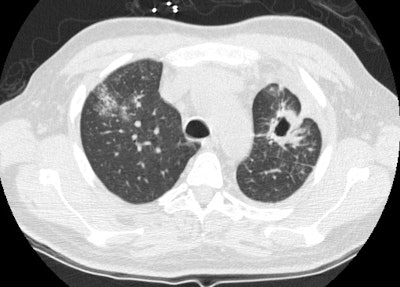

Wegeners: The patient shown in the case below presented with hemoptysis. CXR demonstrated cavitary areas of consolidation in the right mid and left upper lungs (Click CXR to enlarge image). Chest CT revealed cavitary nodules, cavitary areas of consolidation, and non-cavitary areas of patchy parenchymal consolidation. Patient was C-ANCA positive and lung biopsy revealed Wegener's. |

On CT, lung nodules/masses are the most common finding and are seen in 40-90% of patients [12,13,14]. The nodules are usually multiple, bilateral, 2-4 cm in size, usually random in distribution, subpleural (89% of patients), or peribronchovascular (41% of patients), and lack a zonal predilection [1,12,14,15]. Feeding vessels entering the nodular lesions are very commonly identified at CT and reflect the angiocentric nature of the disorder [7]. A CT "halo sign" (a rim of ground glass attenuation surrounding the nodule) may be seen due to surrounding hemorrhage in up to 15% of cases [7,12,13]. The "atoll sign" - a rounded area of consolidation with contral ground-glass attenuation- can also be seen [15]. Cavitation occurs in approximately 25% of nodules larger than 2 cm [12]- typically thick walled with an irregular inner margin [13] (other authors suggest cavitation can occur in up to 50% of nodules larger than 2 cm [15]). Nodules may regress and reappear spontaneously. With treatment, approximately 50% of the nodules resolve, 40% diminish in size, but leave residual damage, and 10% remain unchanged [13]. Pleural effusions are noted in 5-50% of cases, typically the result of pleural involvement.